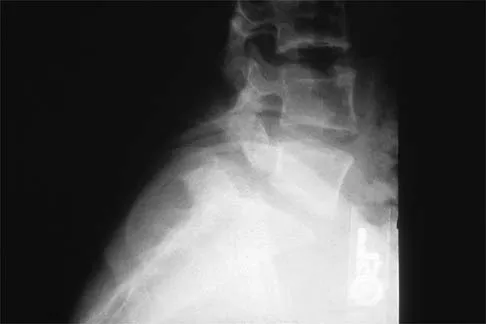

Question 1High Yield

A 28-year-old man sustained a fracture-dislocation of T8 in a motor vehicle accident 1 week ago. The injury resulted in complete paraplegia. Management should consist of

Explanation